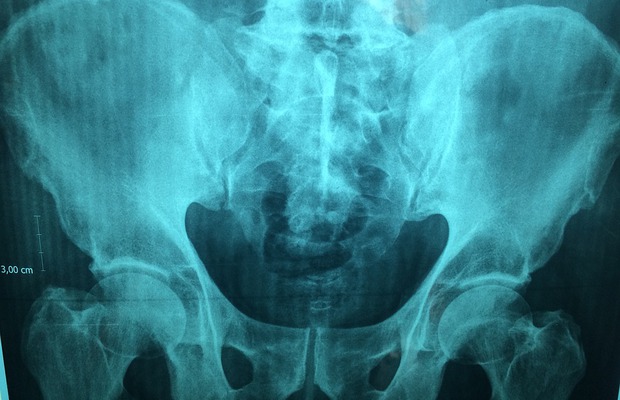

Рентгенография органов брюшной полости

Традиционный диагностический метод клинической медицины для выявления патологий органов брюшной полости

Метод основан на локализованном облучении минимальной дозой рентгеновских лучей, в результате которого получаются проекционные изображения внутренних структур организма. К самым распространенным видам рентгеновского исследования относятся обзорный рентген брюшной полости и контрастная рентгенография.

Обзорный рентген брюшной полости доказал свою диагностическую эффективность. Исследование обязательно назначается в случаях предполагаемой непроходимости кишечника, при нарушениях целостности (перфорации) его стенок или прободении других органов брюшной полости. Обзорный рентген брюшной полости может показать некоторые повреждения органов; наличие в почках, желчном и мочевом пузыре посторонних предметов, патологических образований (опухолей, кист, гематом) и конкрементов (камней); присутствие газов и жидкостей (в том числе крови) в кишечнике и брюшной полости и их локализацию, а также патологическое скопление отходов метаболизма в толстом кишечнике.